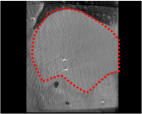

An example of CT/CBCT and MR/CBCT registration results are shown in figures 3 and 4, respectively. For both cases, the CBCT image (first column) was acquired intra-operatively after needle insertions and was employed as a reference for image registration. The pre-operative image is displayed before registration (second column), after PM-EA (third column) and after PM-EA+Evo (fourth column). The occurrence of patch shifts is reported for each spatial direction in panels (m–o): for each histogram, the shift with maximal occurrence is shown by the red dashed line. For panels (a–l), a ROI — manually defined on the CBCT image/encompassing the liver — is shown using red dash lines. Our visualization shows an improved correspondence of the contour of the liver with the manually defined liver boundary when the PM-EA solution is employed (see 3(c,g,k) and 4(c,g,k)). Moreover, an even better correspondence of the contour is observable using the PM-EA+Evo solution (see 3(d,h,l) and 4(d,h,l)).

Trans.

[X-Y]

CBCT

(a)

MRI / No registration

(b)

MRI / PM-EA

(c)

MRI / PM-EA+Evo

(d)

Sag.

[X-Z]

(e)

(f)

(g)

(h)

Cor.

[Y-Z]

(i)

(j)

(k)

(l)

(m)

(n)

(o)